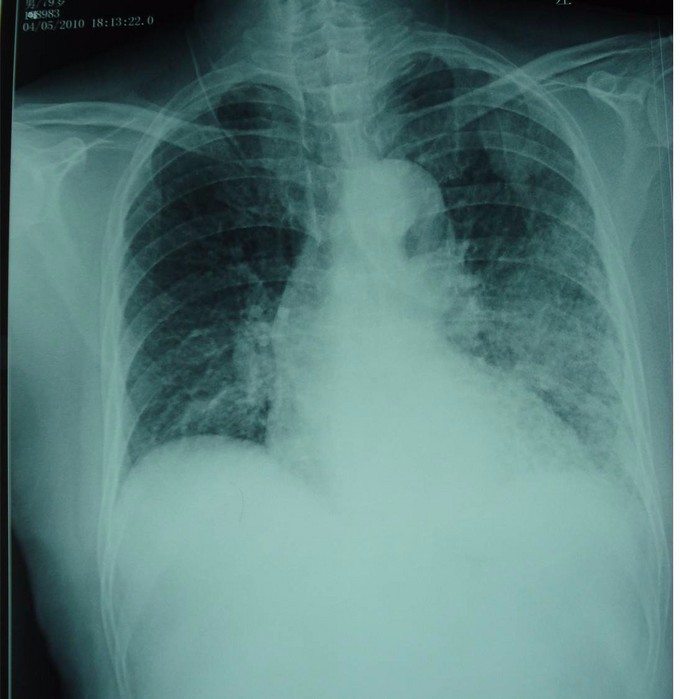

男,79岁,反复咳嗽50余年,喘气3年余,发热一天入院。 近50余年反复咳嗽咳痰,冬春季易发,抗感染治疗可好转,近3年出现喘气。一天前外出扫墓受凉,感全身乏力,精神差,发热,T39.1℃, 伴咳嗽、心慌、胸闷,喘气加重。无咽痛、鼻塞、流涕。 有肺结核病史,血压偏低史,吸烟史50余年,10-20支/日,余下无特殊。

体格检查:T39℃, R 24 bpm,P 88 bpm,BP 150/64 mmHg。唇微绀,急性热病容,双肺可闻及湿罗音,左侧为甚。血常规:WBC6.6×109/L,N78.8%, L18%. HB102g/L , PLT133×109/L ; pH7.5, PCO2:29mmHg,PO2:64mmHg AST59u/L, GGT57u/L, 白蛋白34.9g/L, 球蛋白44.6g/L, A/G0.79, Tbil 34.4umol/L, BUN9.33mmol/L,Cr146.5umol/L Glu7.93mmol/L 痰涂片:G+球菌,G-杆菌 尿常规:蛋白++

诊断:肺炎链球菌肺炎 治疗:卧床休息,青霉素G静注,补充足够蛋白质、热量及维生素。密切监测病情变化,注意防止休克

肺炎链球菌肺炎是由肺炎链球菌所引起的肺实质性炎症。通常起病急骤,以高热,寒战,咳嗽,血痰及胸痛为特征。在X片胸片中呈肺段或肺叶急性炎性实变。一经诊断即应给予抗菌药物治疗,不必等待细菌培养结果。首选青霉素G,用药途径及剂量视病情轻重及有无并发症而定。